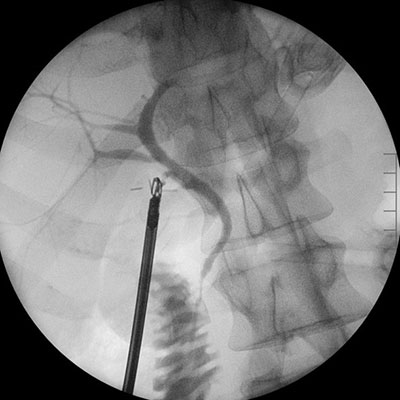

An intraoperative cholangiogram, an X-ray of the bile ducts, is often performed during the surgery to check for any stones that may have moved into the bile duct. If stones are found within the bile ducts, they are removed either during the surgery using a small basket or, in most cases, with a follow-up procedure called an ERCP (Endoscopic Retrograde CholangioPancreatography) the next day.